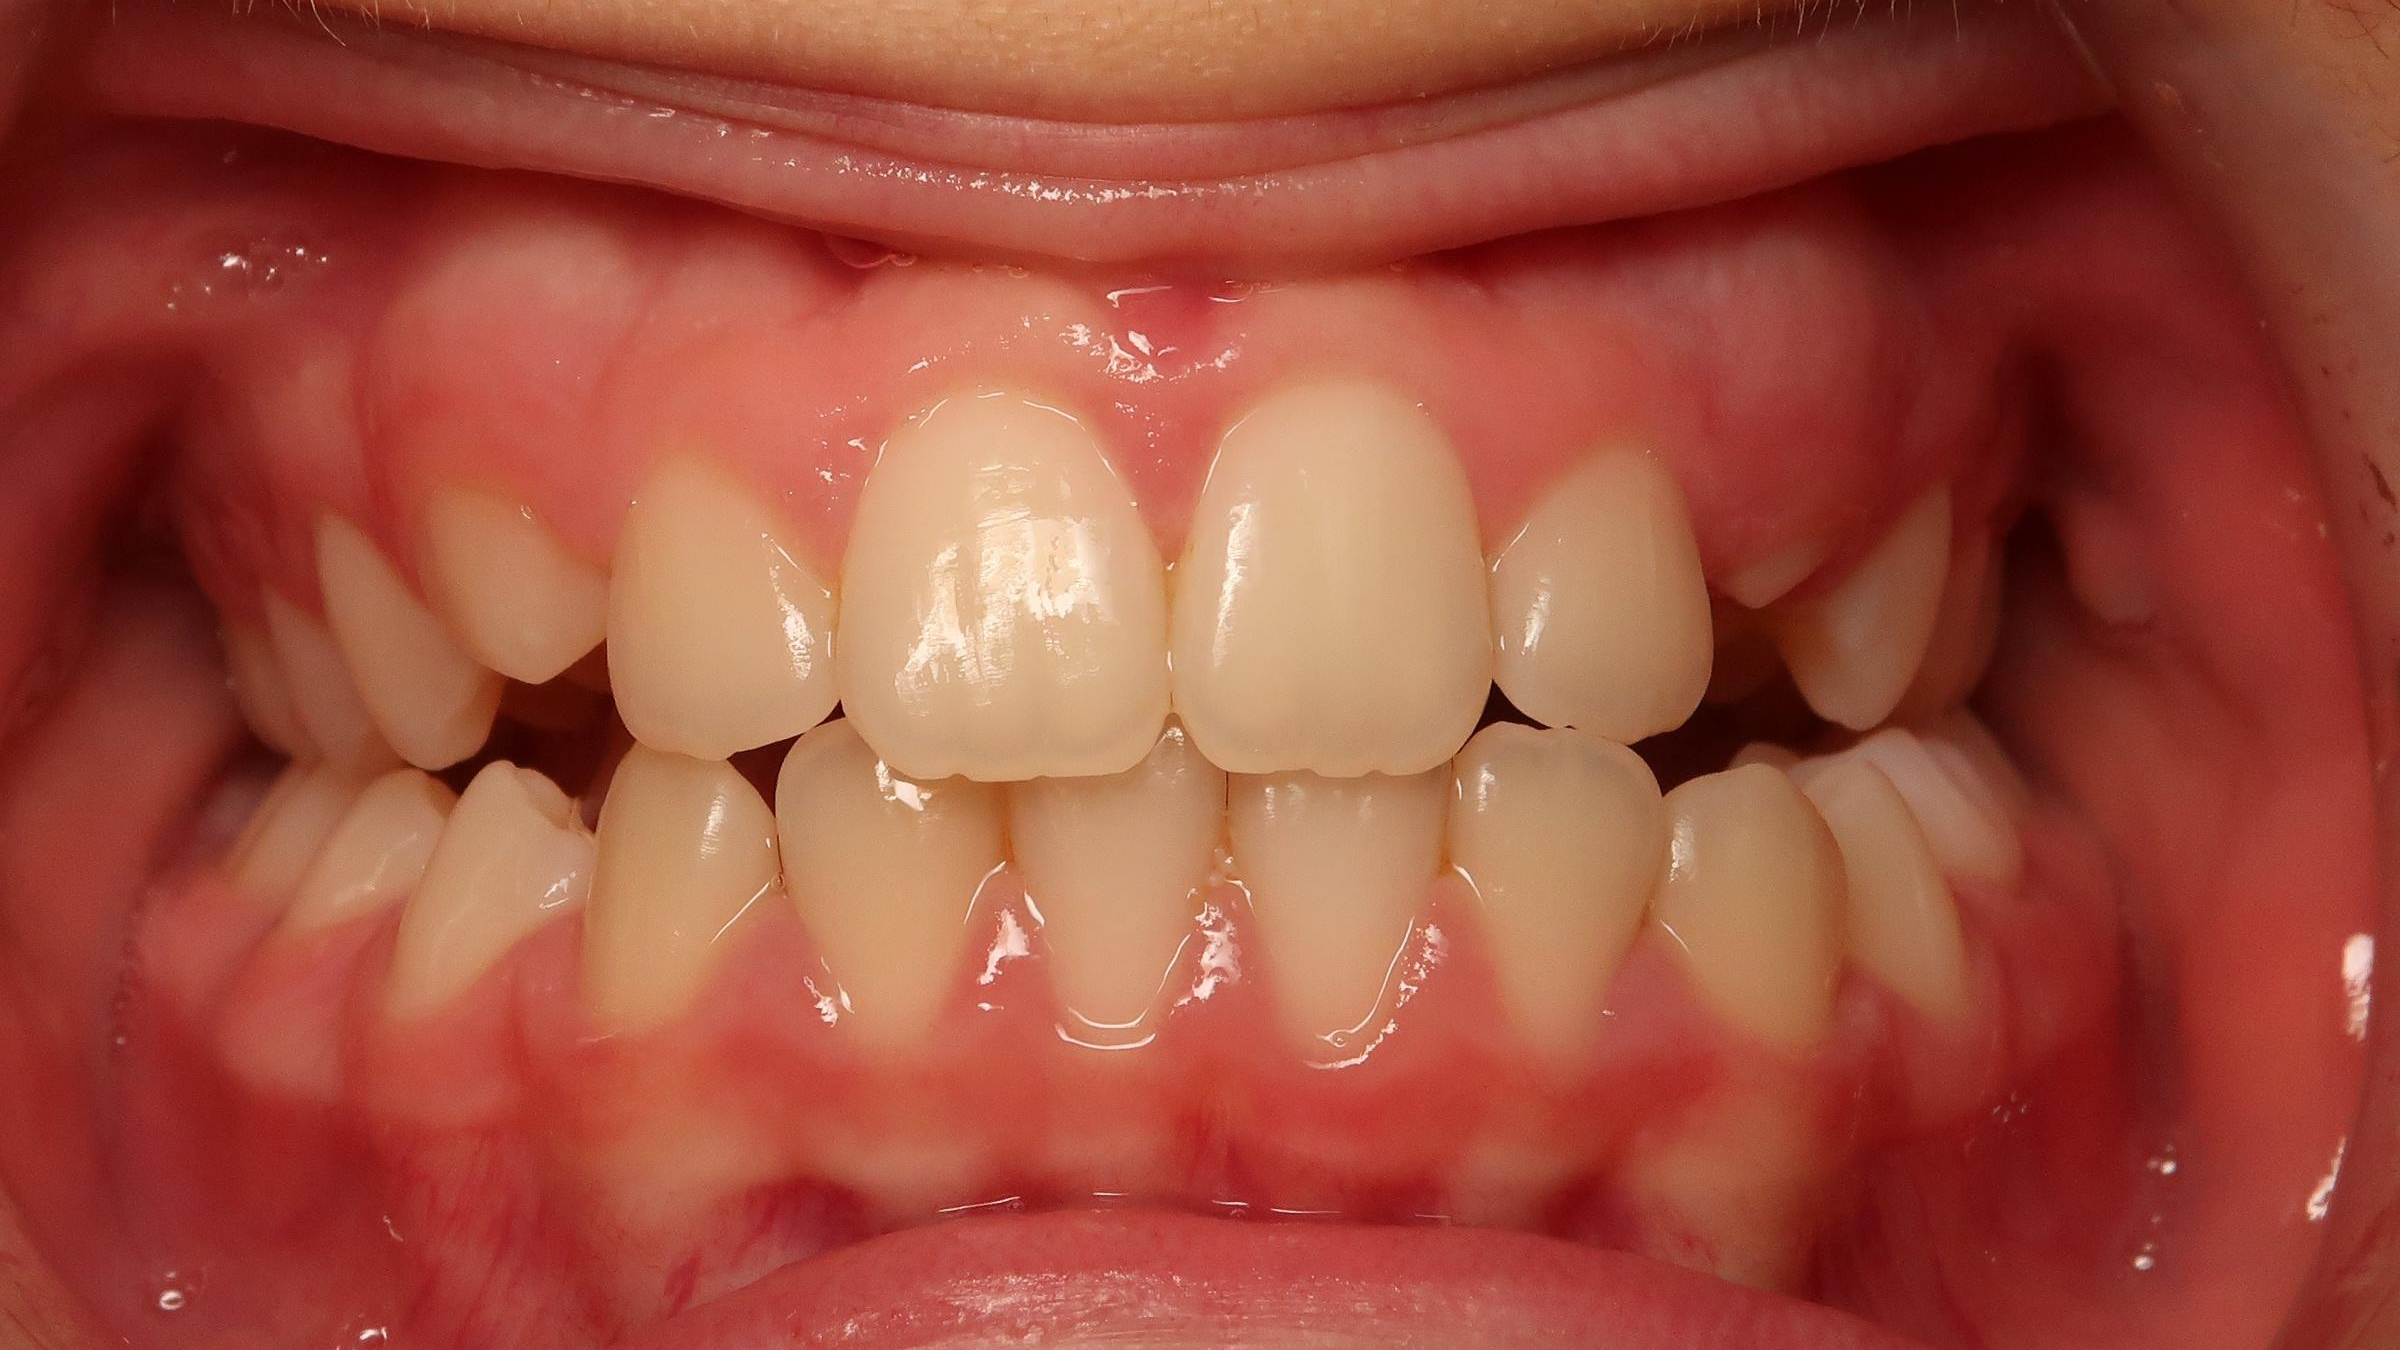

appareillage sectionnel multibagues pendant 18 mois

surveillance évolution de la dentition en cours